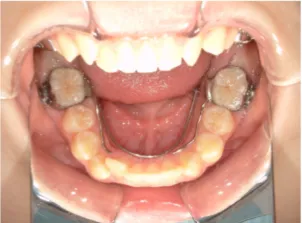

治療中➁小6:QH・BHでアーチ形態改善・上顎前歯を並べる

| 行ったご提案・診断内容 | 生え変わりが終わってなくマルチブラケット法による咬合治療には早い時期のため、顔立ちの成長を促す目的で歯列弓(アーチ)の拡大と前歯を並べながら永久歯が生えるのを待ち、咬合治療開始時に再診断で抜歯、非抜歯を最終検討する提案をしました。 再診断時(写真②)、歯列の拡大と上顎前歯の並べ替えはされていましたが八重歯となったため抜歯、非抜歯を検討しました。 口元は特に問題がなく非抜歯で八重歯を改善するためのスペースを作ることが可能なため非抜歯治療を提案しました。 治療は、 ・拡大および上顎左右6を遠心移動させてスペースを作る 予定装置 |